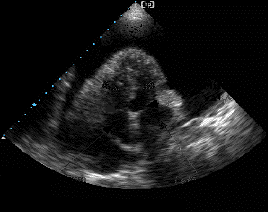

Semne ecocardiografice:

lichid pericardic in cantitate mare (evidentiaza si dispunerea topografica a acestuia),

reducere a amplitudinii excursiei DE si pantei EF a valvei mitrale la prima diastola din inspir,

variatie inspir-expir > 40% a amplitudinii excursiei DE a valvei tricuspide,

colaps AD, VD (protodiastolic) si AS,

congestie 'fixa' a VCI (scadere < 50% in diametru proximal la inspir profund).

EcoCG in tamponada cardiaca